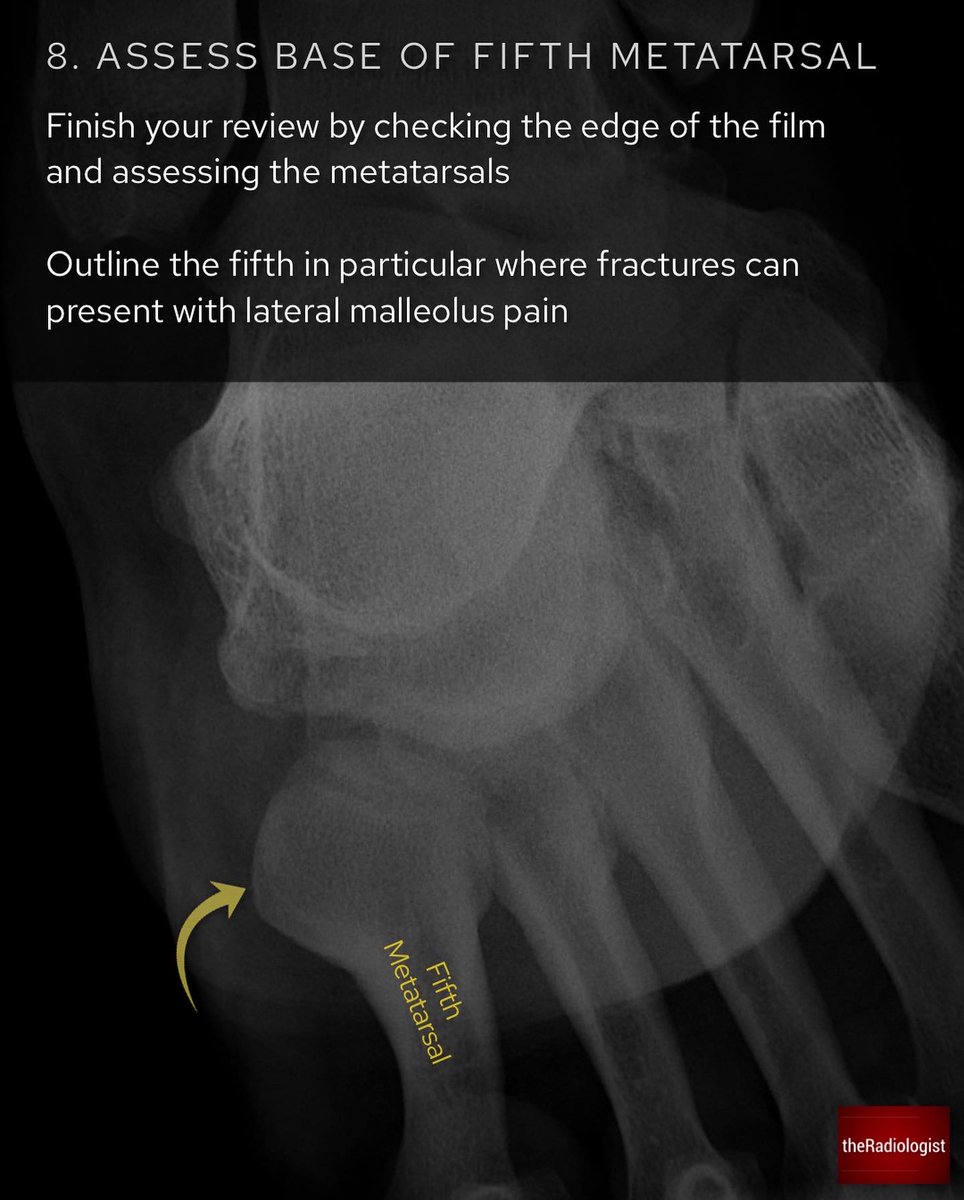

Ankle X-Ray mortise view: anatomy and strategy (1/3)